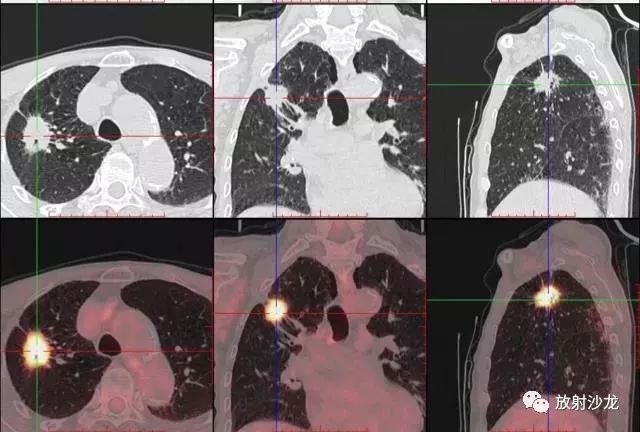

PET-CT等于PET+CT,包含PET(功能分子影像)與CT(解剖影像)的最優(yōu)化組合;即同時(shí)具有PET和CT的功能,但它絕不是二者功能的簡單疊加,因?yàn)镻ET與CT優(yōu)勢互補(bǔ),“1+1>2”。PET-CT除了具備PET和CT各自的功能外,其獨(dú)有的融合圖像,將PET圖像與CT圖像融合, 可以同時(shí)反映病灶的代謝,可以早期診斷疾病的同時(shí),明顯提高診斷的準(zhǔn)確性。

18F-FDG(氟脫氧葡萄糖)是葡萄糖的類似物,是臨床最常用的顯像劑;18F-FDG能反映體內(nèi)葡萄糖利用狀況。腫瘤細(xì)胞內(nèi)可積聚大量18F-FDG,但是18F-FDG僅僅是葡萄糖類似物,腫瘤細(xì)胞攝取后不能進(jìn)一步代謝,屬于“只進(jìn)不拉”,能在腫瘤細(xì)胞內(nèi)積聚,經(jīng)PET-CT顯像可顯示腫瘤的部位、形態(tài)、大小、數(shù)量及腫瘤內(nèi)的放射性分布。同時(shí)腫瘤細(xì)胞的原發(fā)灶和轉(zhuǎn)移灶具有相似的代謝特性,一次注射18F-FDG就能方便地進(jìn)行全身顯像,18F-FDG PET-CT全身顯像對于了解腫瘤的全身累及范圍具有獨(dú)特價(jià)值。